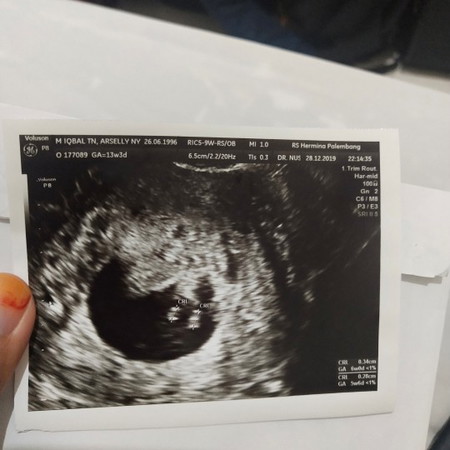

Bingung harus mulai cerita dari mana. Postingan sebelumnya sudah pernah cerita kalau kehamilan kemarin sempat bermasalah. Usia kehamilan yang seharusnya sudah 8 minggu namun janinnya tetap menunjukkan usia 6 minggu. Sudah berapa kali pindah2 dokter obgyn karena seharusnya diusia 6-8 minggu itu janin sudah terlihat dan terdengar detak jantung melalui usg transv. Salah satu dokter bilang kalau ternyata saya Blighted Ovum (hamil kosong) tapi karena sebelumnya saya pernah usg dan terlihat titik janin, saya dan suami tetap berusaha mencari opini dokter yg lain. Akhirnya kami memutuskan untuk langsung cek ke dokter obgyn subspesialis fetomaternal yang menangani langsung masalah janin. Alhasil, dokter tersebut bilang kalau terdapat janin dalam kandungan namun sayangnya berhenti berkembang pada usia 6 minggu. Dan yang lebih sedihnya dokter bilang kalau bakal janinnya ada 2. Another heart break? akhirnya dokter menyarankan untuk dikuret karena sudah tidak ada harapan lagi untuk berkembang mengingat sudah tidak ada alairan darah lagi menuju janin. Dokter bilang penyebabnya bisa terjadi karena kelainan kromosom atau faktor virus. Jadi saya disarankan untuk cek lab torch. Hasilnya igm tokso saya positif. Kemudian dokter kembali menyarankan cek aviditas igg nya dan ternyata hasilnya tinggi. Dokter berpendapat bahwa sistem kekebalan tubuh saya sudah baik, jadi tidak perlu terapi obat untuk penyembuhan tokso sehingga kemungkinan penyebab janin gagal berkembang karena kelainan kromosom. Namun untuk antisipasi kehamilan berikutnya disarankan untuk diiringi dengan konsumsi antibiotik. Sekarang sudah hampir 2 bulan pasca kuret, saya masih suka sedih kalo liat foto usg si calon dedek kemarin? mohon doanya ya bunda semoga saya dan suami kembali diberi kepercayaan oleh Allah untuk menjadi orang tua..